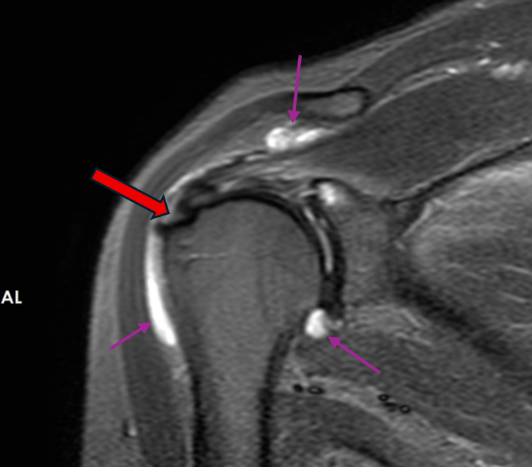

冈上肌肌腱滑囊侧部分撕裂,伴滑囊、关节囊积液(紫色箭头所示)